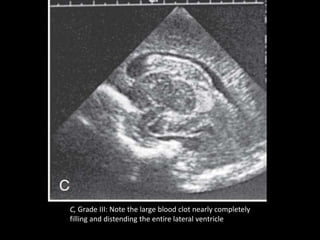

C, Grade III: Note the large blood clot nearly completely

filling and distending the entire lateral ventricle

C, Grade III:Note the large blood clot nearly completely filling and distending the entire lateral ventricle